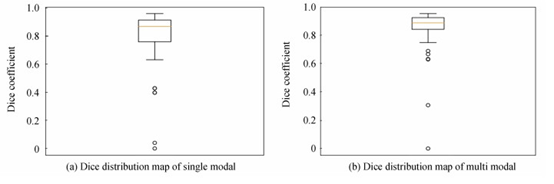

图 8为测试集57例样本的评价指标Dice分布图,对比图 8(a)和(b)可知,单模态网络中有4例样本远离集群点,而多模态仅有2例样本远离集群点.

图 8 脑肿瘤测试集Dice分布

表 1为不同模态脑肿瘤检测网络训练集57例样本的三种评价指标量化分析对比.可知,多模态脑肿瘤检测网络的三种评价指标Dice、SN和SE分别提升了4.79%、0.15%和0.06%,从测试集的量化结果表明多模态的脑肿瘤检测方法更佳.

表 1 不同模态脑肿瘤检测三种评价指标对比

从图 10所展示的脑肿瘤测试集57例病例样本的Dice指标分布可知,与图 8(b)相比,结合了实例归一化的脑肿瘤检测结果最低的Dice值也可达到0.41,较3.2.1节的实验结果最低Dice值提升了约0.4,也仅有两个严重的远离集群点.